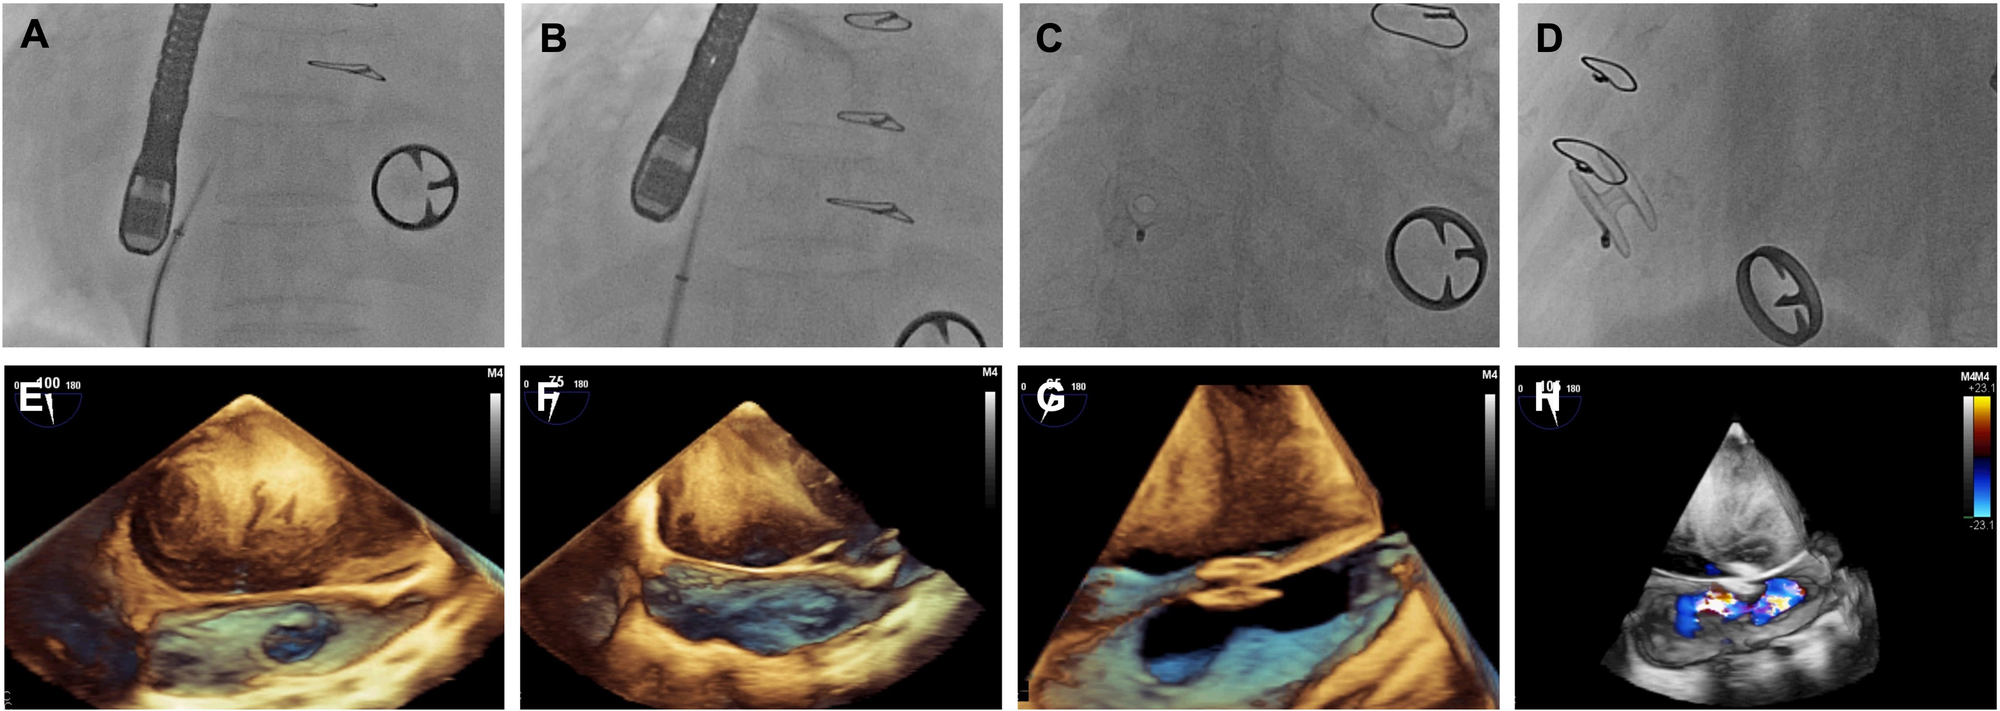

The procedures were performed under general anesthesia. Standard trans-septal puncture of the interatrial septum was carried out by fluoroscopy and transesophageal echocardiography (Figure 1). The delivery system was advanced via the wire into the LA, the left side of the D-Shant device was opened, and the delivery system was retracted to make contact with the septum on the LA side. The right half of the device was then placed into the right atrial side of the septum. The delivery system and guiding wire were then removed.

Figure 1

Images of D-shant device implantation. (A) x-ray and (E) transesophageal echocardiography (TEE) show the atrial septal position; (B) x-ray and (F) TEE guide atrial septal puncture; (C) x-ray and (G) TEE show release of the D-Shant device; and finally, (D) x-ray and (H) TEE color Doppler confirm the position of the D-Shant device and left-to-right shunting.